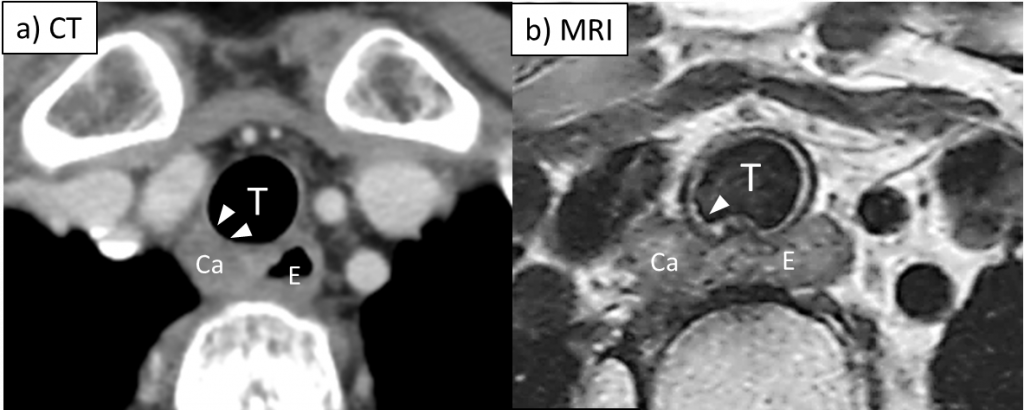

③食道癌における壁深達度診断の世界的標準モダリティはCT検査であるが、層構造の判定が難しいため診断は極めて難しいことが臨床的に問題となっています。心呼吸同期と画像精度が飛躍的に向上した3.0テスラMRIの登場により、その存在価値は高まっており、本研究ではMRIの診断および腫瘍悪性度評価の有用性を多施設前向き研究で明らかにすることを目的とします。

Impact of MRI on the post‑therapeutic diagnosis of T4 esophageal cancer,

Takashi Harino, Makoto Yamasaki, et al

Esophagus, 2023 Oct;20(4):740-748. doi: 10.1007/s10388-023-01010-2.